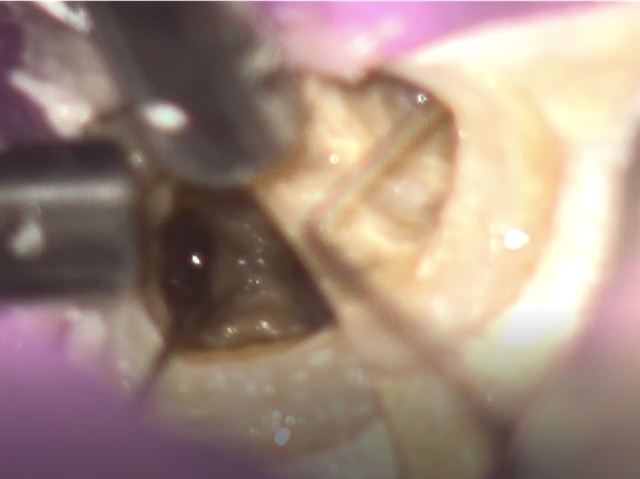

かぶせ物が不適であること(青矢印部)、近心根に根尖病巣があること(青枠部)、根充剤がかなり太いため(赤矢印部)歯質が薄くなっていることなど問題点がいくつかありましたが、他院で治療をしたばかりであり、また上記の条件から再治療には抜歯のリスクが非常に高いことから初診時は患者さんと相談し経過観察することになりました。